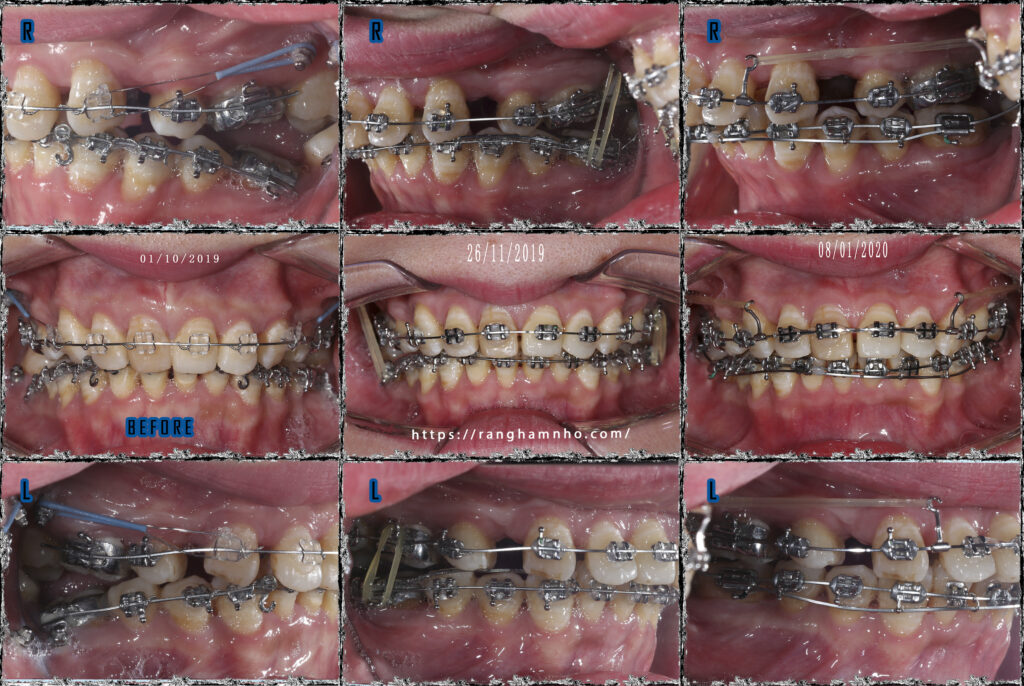

Bệnh nhân nữ sinh năm 1980, đã niềng răng 2 năm tại 1 cơ sở chỉnh nha khác. Đây là một trong những trường hợp niềng răng lỗi rất nặng trên bệnh nhân lớn tuổi. Một case lâm sàng rất thách thức cho bất kì bác sĩ chỉnh nha nào.

Tình trạng hai hàm còn rất nhiều khoảng, hàm trên đã nhổ 2R4, hàm dưới nhổ 2R7- rất khó hiểu cho chỉnh định nhổ 2R7 hàm dưới ở bệnh nhân lớn tuổi trong trường hợp này. Khoảng trống sau nhổ còn rất nhiều, chân răng tiêu rất nhiều sau 2 năm điều trị. Chân răng bật ra khỏi bản xương (mất torque chân răng nặng) cả hai hàm.

Khớp cắn “không có trong sách vở”, toàn bộ nhóm răng sau gần như chỉ chạm nhau ở răng số 5, bệnh nhân phàn nàn không thể ăn nhai, sút cân, mặt hóp- hóp má, hóp thái dương nhiều từ sau khi niềng răng. Vấn để nhả khớp răng hàm một cách không kiểm soát, hở khớp nhóm răng sau rất nhiều. Răng số 8 hàm dưới nghiêng gần rất nhiều.

Chỉnh lại torque nhóm răng cửa, đánh lún và kéo lui nhóm răng trước. Với nhóm răng cửa hàm dưới, do xương ổ răng tiêu rất nặng nên phải tháo mắc cài sớm để hạn chế việc tiêu xương thêm, việc chỉnh torque đưa chân răng vào trong cũng chỉ ở mức độ tương đối, tiên lượng xấu cho nhóm răng này về sau nhưng tiếp nhận điều trị lại với những sai lệch lớn như này bác sĩ cũng không thể làm gì hơn.